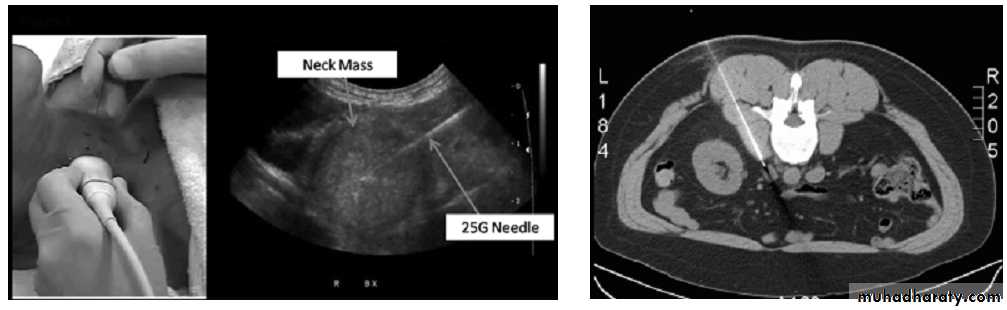

Bronchoscopic bxBiopsy-Guidance

Visual– Superficial localization & body cavities

By imaging

– Deep localization

– US guided bx or FNAC

– CT scan guided bx or